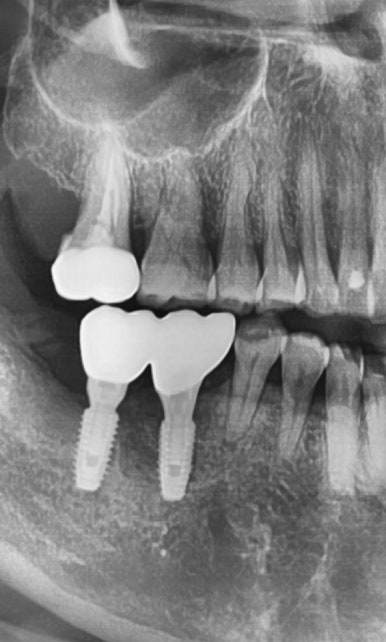

간단한 상악동 수술이 아니라 복잡한 고난이도의 상악동 수술이 필요했는데

상악동을 들어올려 뼈이식을 하고(노란색으로 표시된 부분)

임플란트 2개를 심은 모습입니다. [②로 표시된 부분]

나머지 ①③ 표시된 부분도 원장님께 임플란트 수술을 받으셨습니다.

④로 표시된 부분은 사랑니 발치한 부분입니다.

원장님께 수술 받은 3군데 임플란트 5개 모두 잘 쓰고 계십니다.